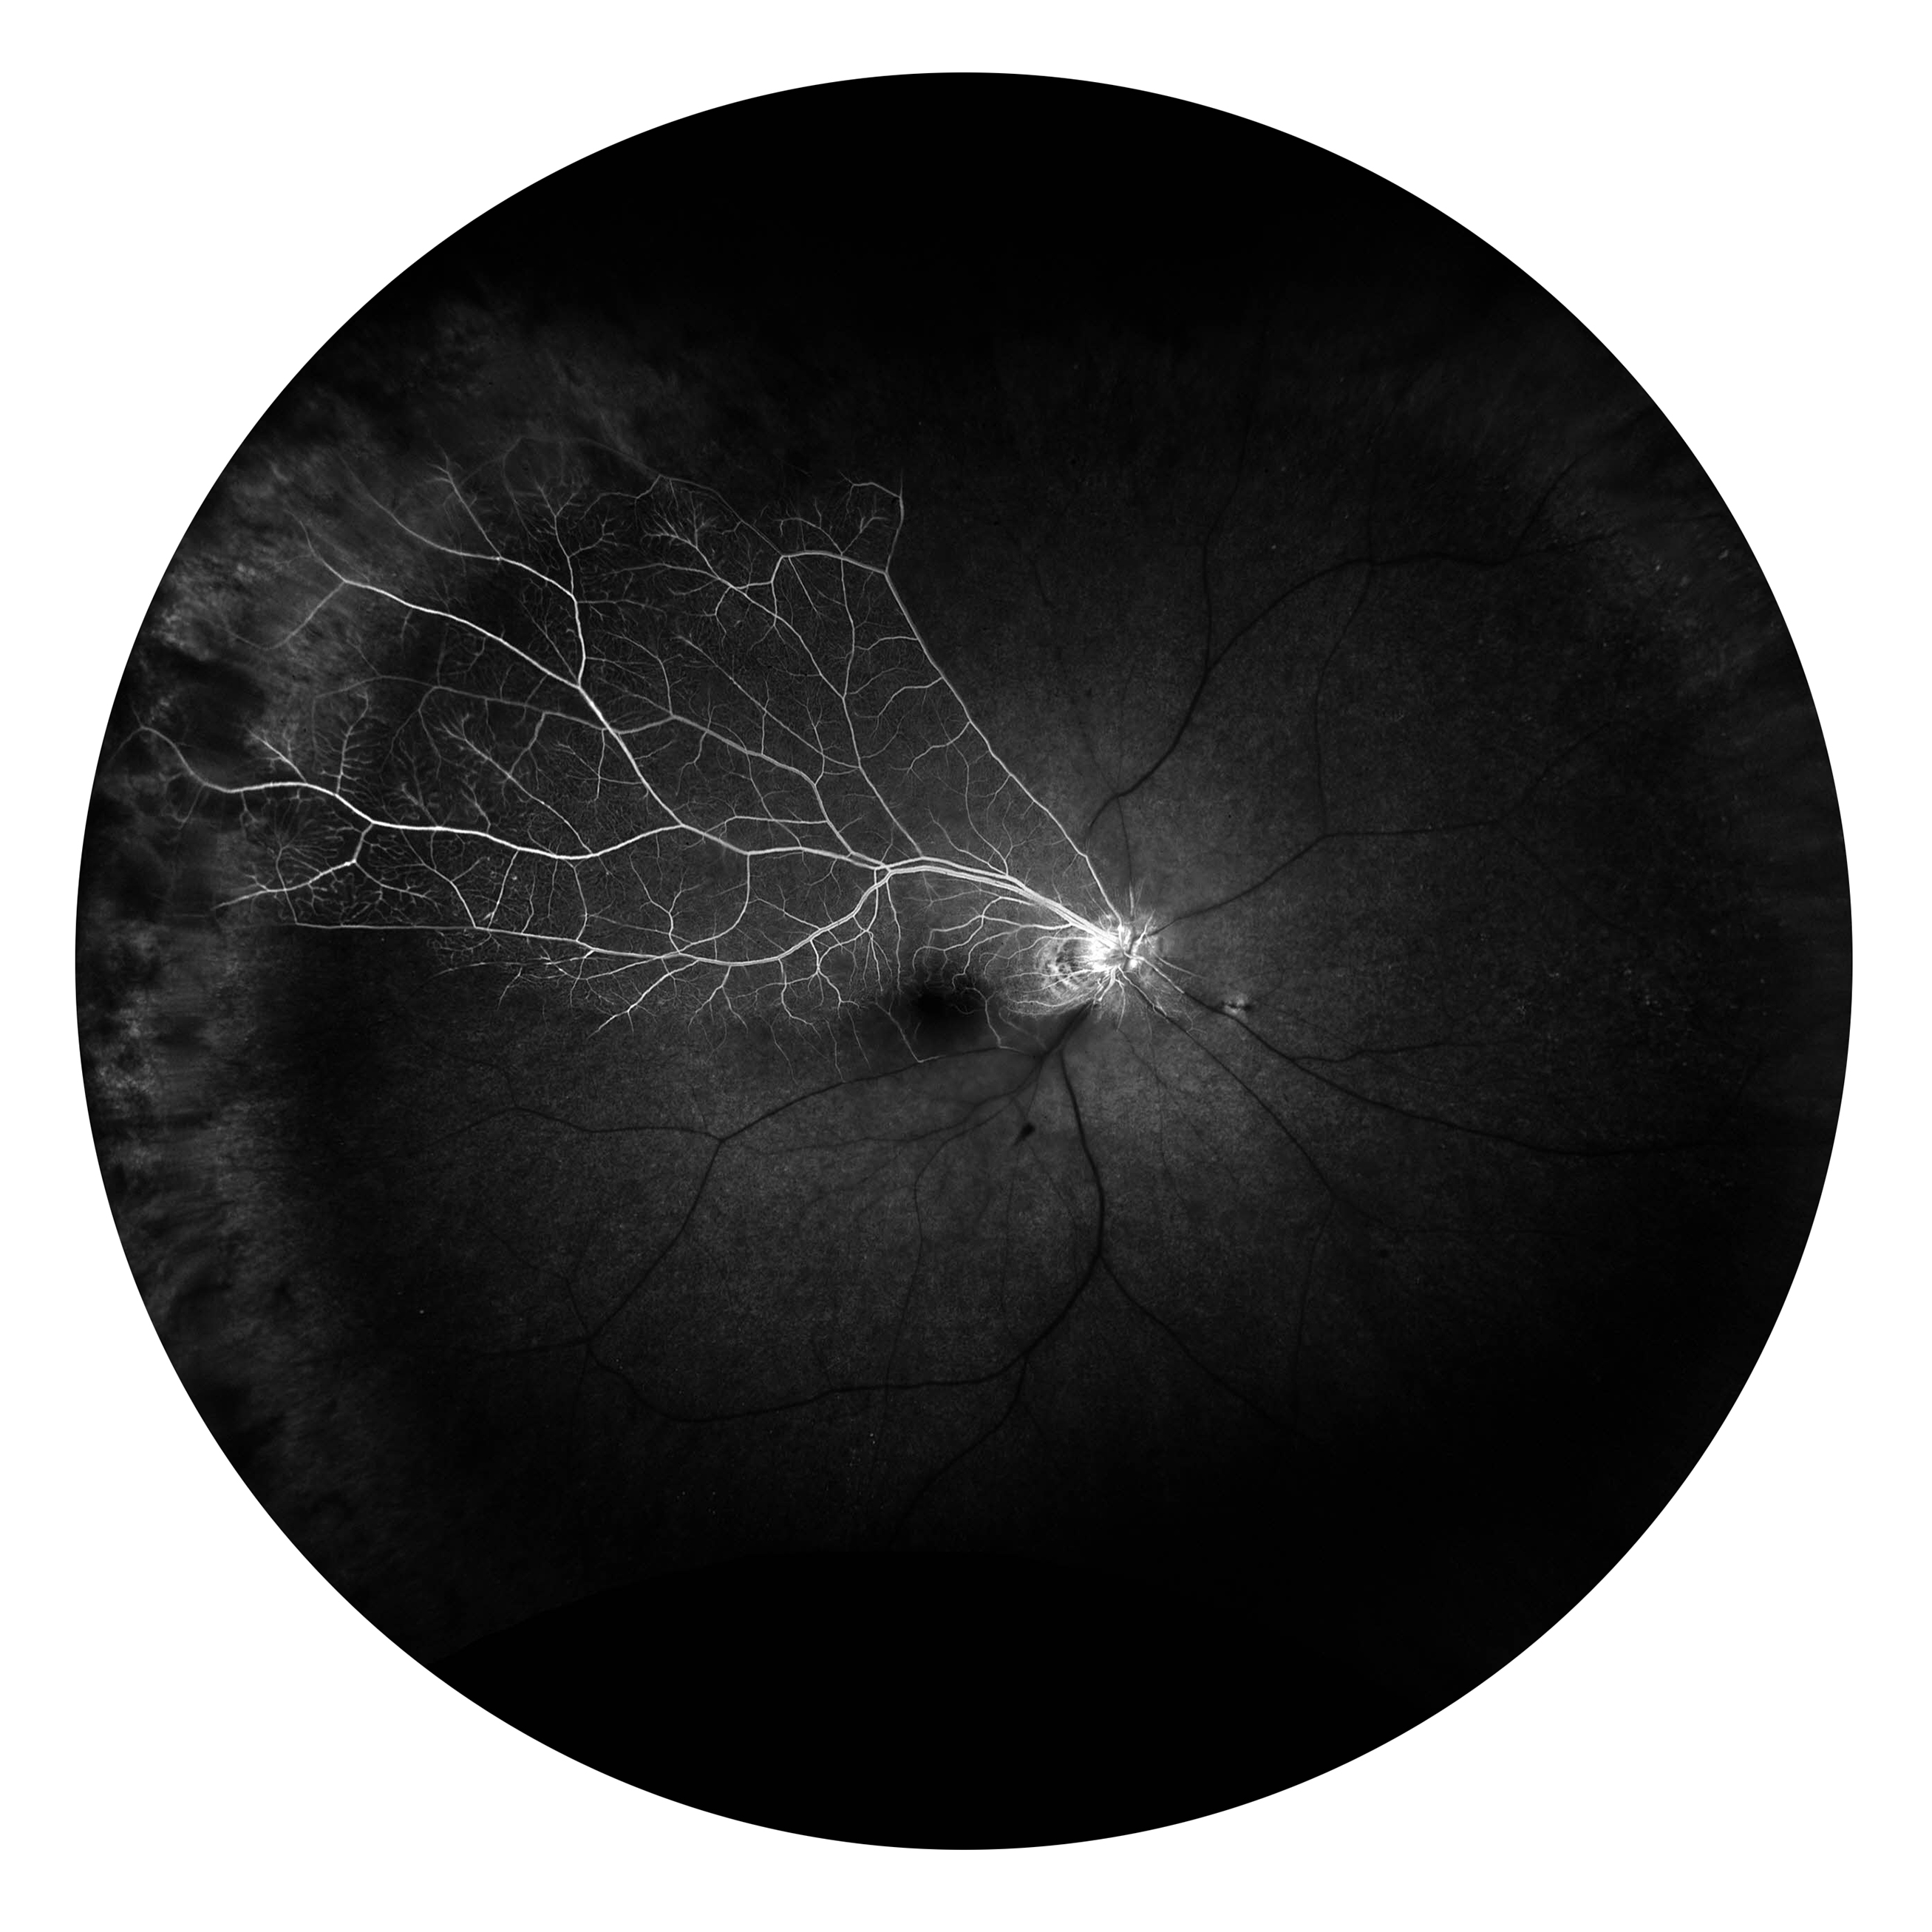

Unknown Presented by Lexy Anoona This photograph received First Place, Fluorescein Angiography (45° - 60°) in the 2025 OPS Scientific Exhibit. Filed Under Cornea OPS Photo